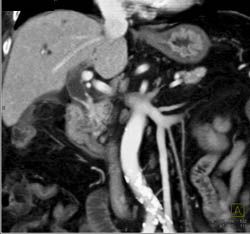

Cholangiocarcinoma of the Distal Common Bile Duct (CBD) Which Is Enhancing- See Full Sequence